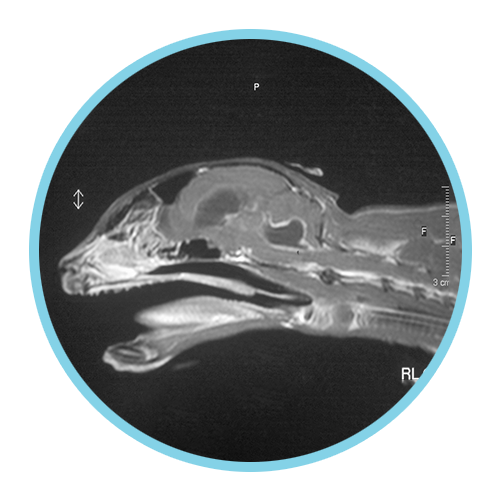

Neurological FIP